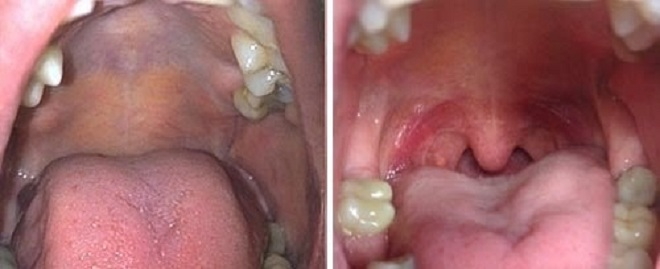

Sự thay đổi của vòm họng khách hàng trước và sau điều trị ngủ ngáy.

Kỹ thuật điều trị ngủ ngáy bằng Fotona 4D rất nhẹ nhàng mà không hề xâm lấn. Sử dụng tia laser chuyên biệt làm co khít chặt lưỡi gà, khẩu cái mềm và mô mềm chung quanh.

Cơ chế hoạt động của Fotona 4D trong điều trị ngủ ngáy: sử dụng hiệu ứng nhiệt không cắt của tia laser Er:Yag kích thích sự tái cấu trúc các sợi collagen và kích hoạt quá trình tổng hợp sợi collagen mới. Từ đó, khiến mô niêm mạc và mô mềm vùng miệng – hầu trở nên co khít giúp mở rộng đường thở, làm cho việc hít thở trong lúc ngủ được tốt hơn.